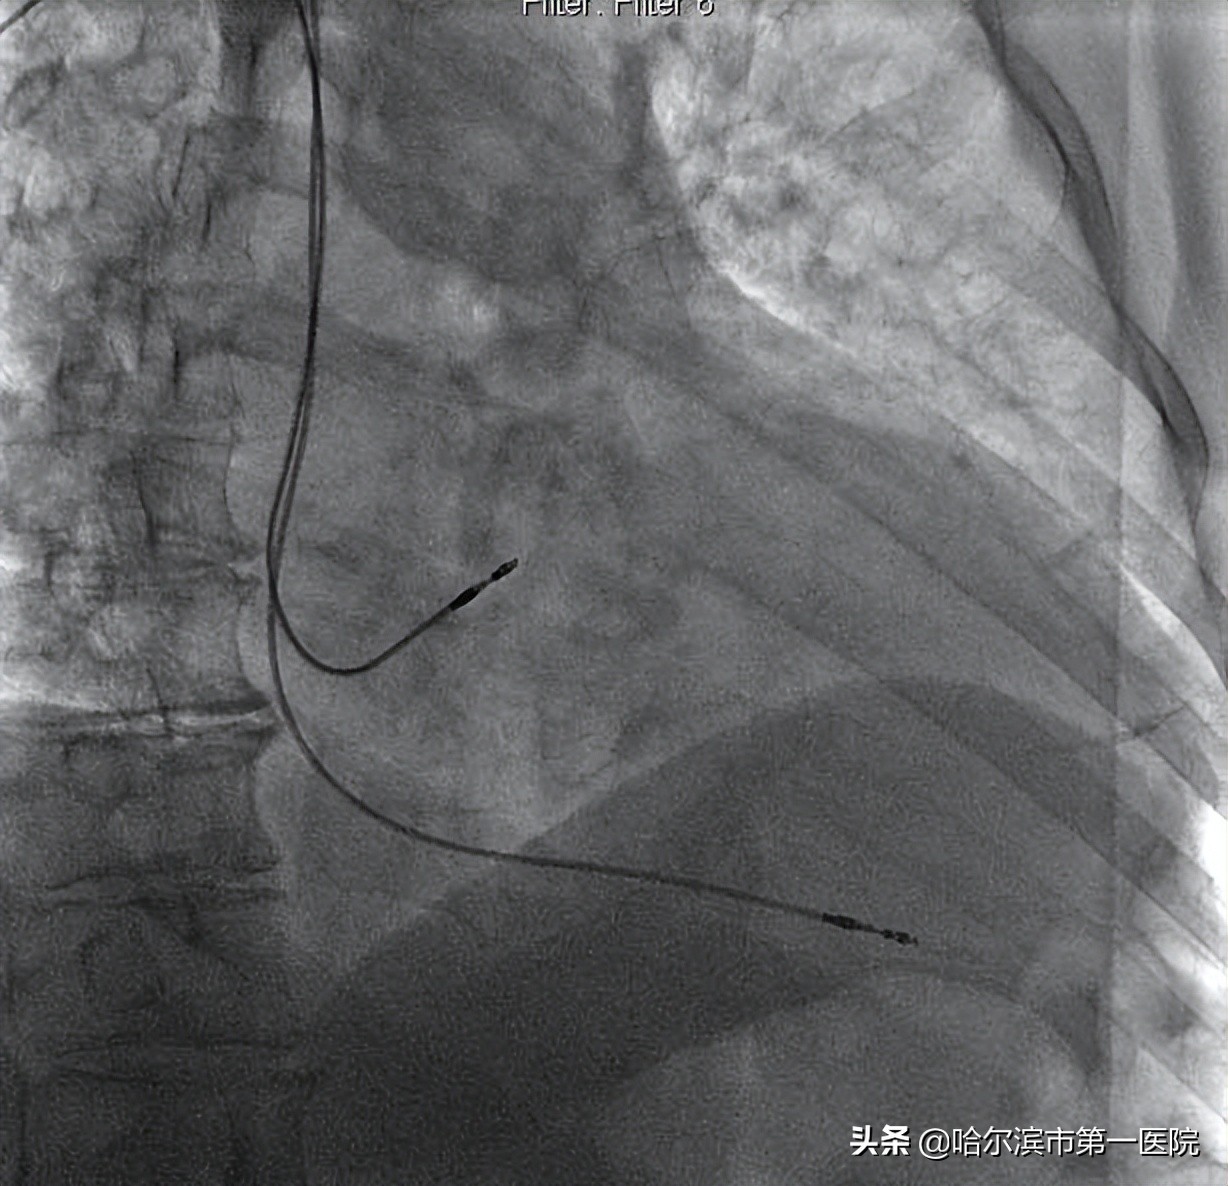

图3 赵侃团队ENDURITY MRI™ 双腔起搏器植入术中

图 4 ENDURITY MRI™ 双腔起搏器术后DSA影像